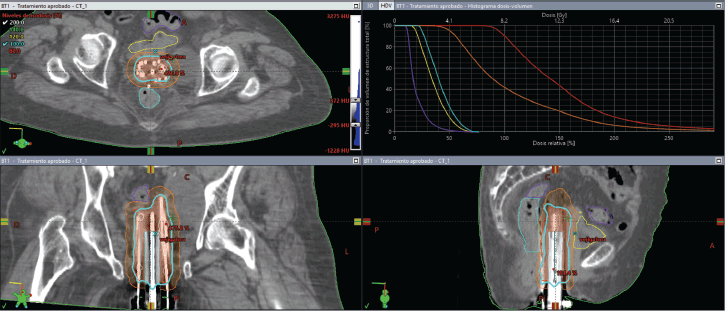

Under spinal anesthesia, the implant procedure involved placing three flexible catheters on each side of the urethra at different depths (roughly 1 cm between each), plus an additional superficial catheter in the central region of the tumour. The catheters were secured with small radiopaque fixation buttons (Figure 2). A post-implant CT scan was performed to confirm the positioning of the catheters relative to the GTV and OAR.

Figure 2. Case 1. The vulvar tumour and the implantation of seven interstitial catheters are observed.